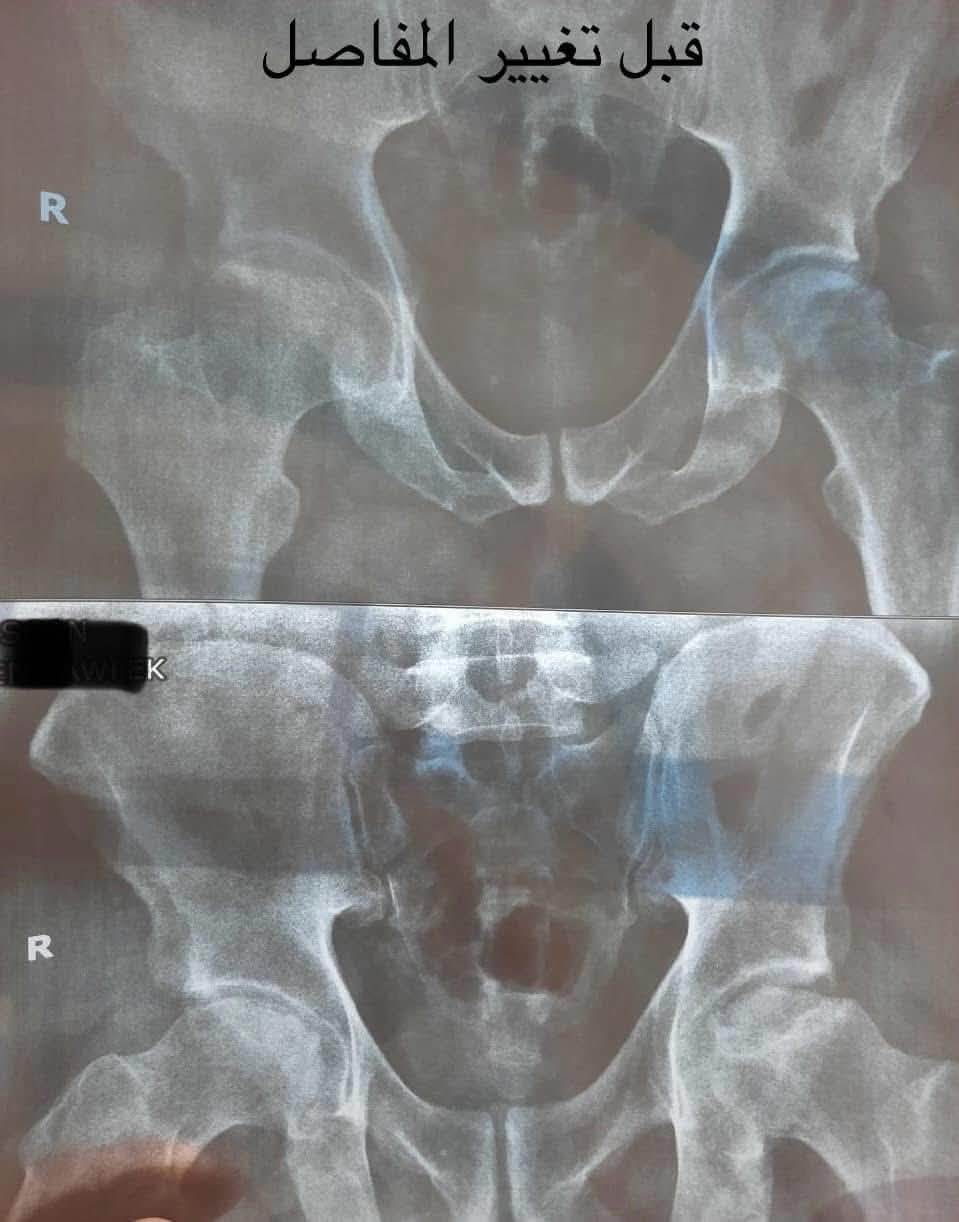

30 عملية تغيير مفصل صناعي بمستشفى الخانكة التخصصي

نجح فريق طبي بمستشفى الخانكة التخصصى بمحافظة القليوبية، فى إجراء 30 عملية تغيير مفصل صناعي.